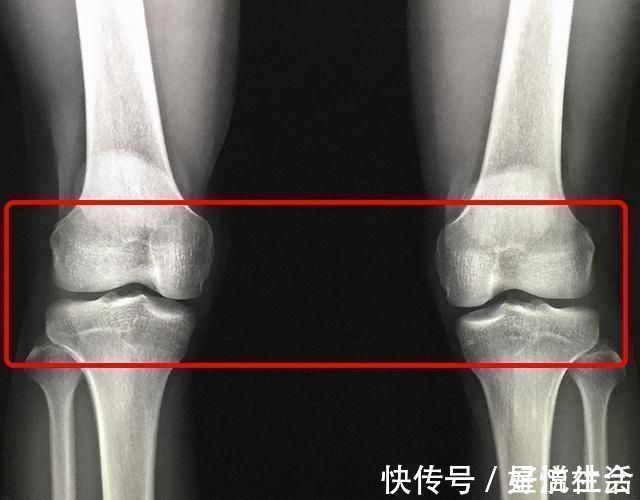

这次趁着自己体检的机会,妈妈悄悄地带孩子到儿科门诊检查。医生说:从遗传学来看,张放应该长到165 cm以上,但一查骨龄,他的骨骺线已基本闭合,最多还能长2-3 cm。这样的结果让妈妈不能接受,希望医生多想办法,但医生却表示无能为力。在排号等待时,刚好看到张放的同学也来体检,医生说:尽管这名同学和张放的情况相似,但他的骨骺线没有完全闭合,身高还有一定的上升空间。见此情景,妈妈更加后悔没早做检查,以致于错失良机。

对“晚长”需要综合考虑孩子是否属于真正的“晚长”,不能只凭表面的现象,更不能想当然。要先检查孩子的骨龄,看骨龄的发育是提前还是落后,然后再结合第二性征的发育情况,在排除性腺发育方面的疾病以后,再进行综合判断。因此,父母要关心孩子的生长和发育情况,发现异常要尽早带孩子进行专业检查,并针对其发育提前和迟缓等现象,由医生采取医学手段进行有效干预,可能会取得一定的效果。如果骨骺线完全闭合,医生也会束手无策。